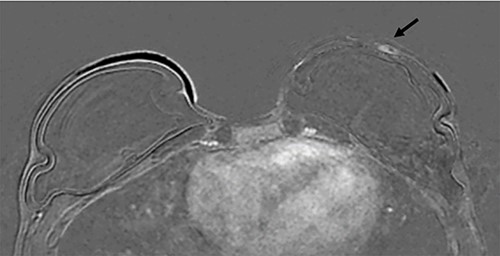

A 37-year-old Caucasian woman underwent a left therapeutic skin-sparing mastectomy and sentinel lymph node biopsy and a simultaneous right risk-reducing skin-sparing mastectomy in 2016. She had bilateral immediate subpectoral breast reconstruction with Becker-35 expandable implants combined with SurgiMend® (Integra LifeSciences, Princeton, NJ) acellular dermal matrix (ADM). Histology revealed 45 mm of high-grade ductal carcinoma in situ (DCIS) with three foci of invasive carcinoma No Special Type (NST) measuring 4, 2 and 1.6 mm in size (Fig. 1). The disease was ER positive, PR-negative and HER-2 negative, the two sentinel nodes were disease-free and the patient received tamoxifen as adjuvant therapy.

Axial fat-saturated post contrast Magnetic Resonance Imaging (MRI) of the breasts. There is extensive stippled non mass like enhancement throughout the inferior and central left breast with type 1 benign kinetics in keeping with DCIS.